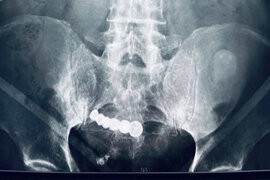

73 yaşlı qadının qarnından 35 illik DÖL ÇIXARILDI

Həkimlər qarın ağrısından şikayət edən yaşlı qadının bətnində 35 yaşlı daşlaşmış döl aşkar ediblər. xəbər verir ki, bu barədə "Daily Star" xəbər portalı məlumat yayıb. Belə ki, 73 yaşlı qadının mədəsinin rentgen müayinəsi zamanı həkimlər təxminən yeddi aylıq və 2 kq ağırlığında olan dölün şokedic